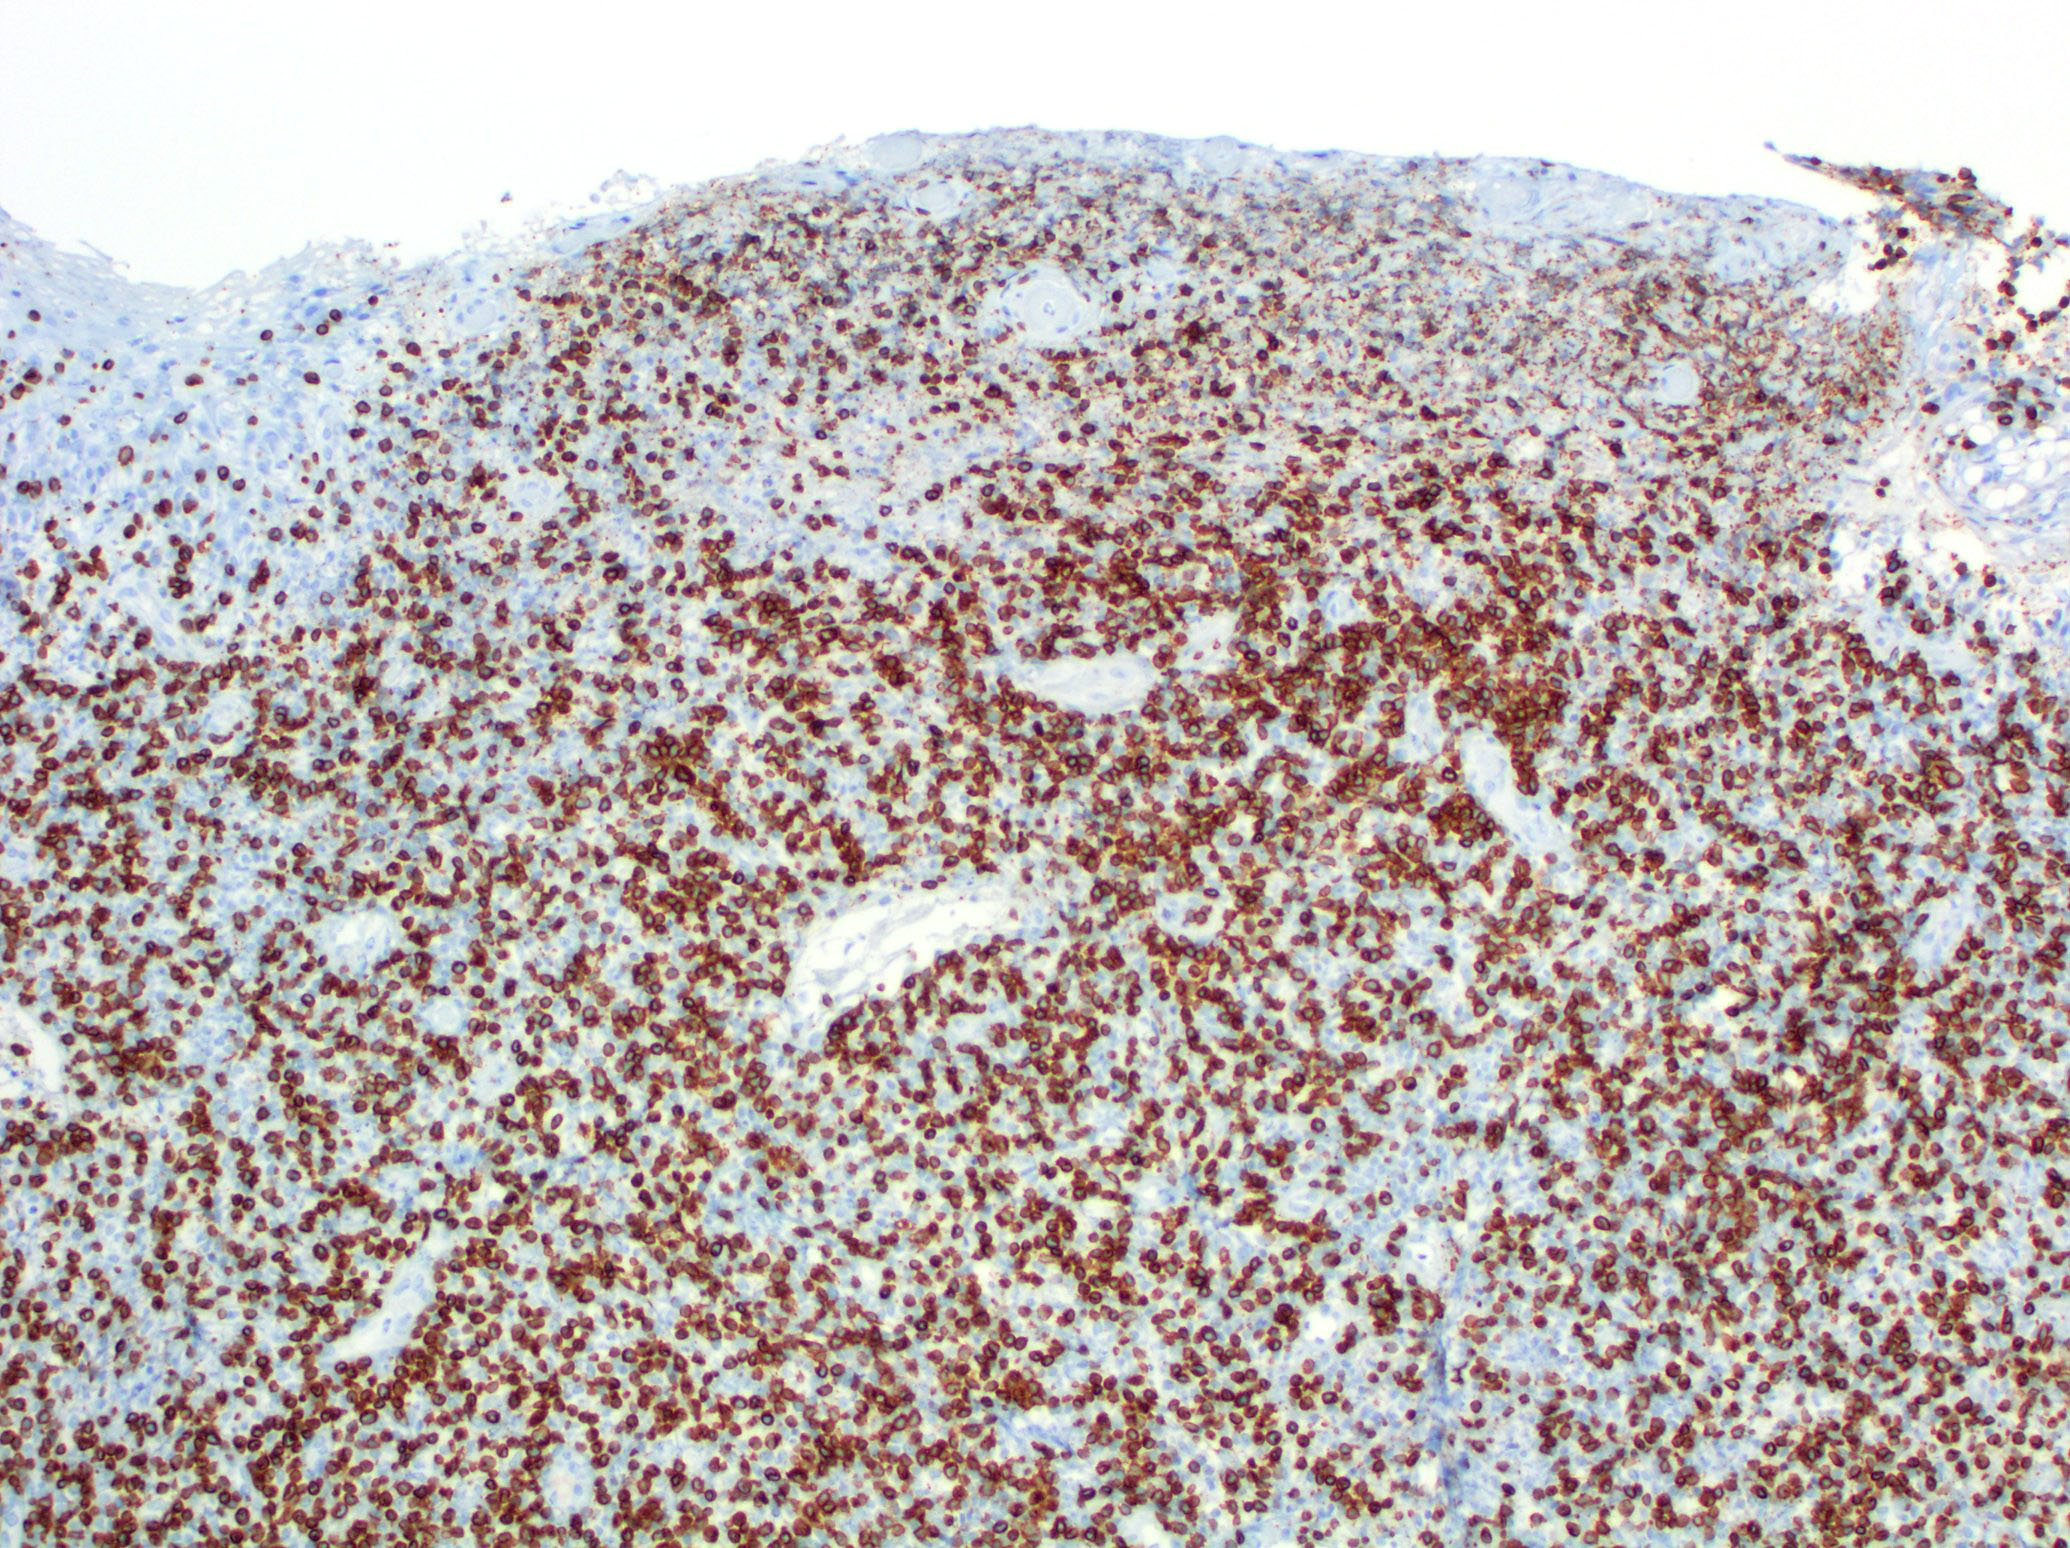

Microscopic (histologic) images

Contributed by Roberto N. Miranda, M.D.

Positive stains

- Activate T helper phenotype (Semin Diagn Pathol 2017;34:22)

Immunohistochemical Summary of LyP Types

*All cases are anaplastic lymphoma kinase - 1 (ALK-1) negative

| Type of LyP | Reference | CD2 | CD3 | CD4 | CD5 | CD7 | CD8 | CD30 | Other markers |

| Type A | Blood 2019;133:1703 | +/- | + | + | +/- | +/- | - | + | TIA1+ |

| Type B | Blood 2019;133:1703 | +/- | + | + | +/- | +/- | - | - | TIA1+ |

| Type C | Blood 2019;133:1703 | +/- | + | + | +/- | +/- | - | + | TIA1+ |